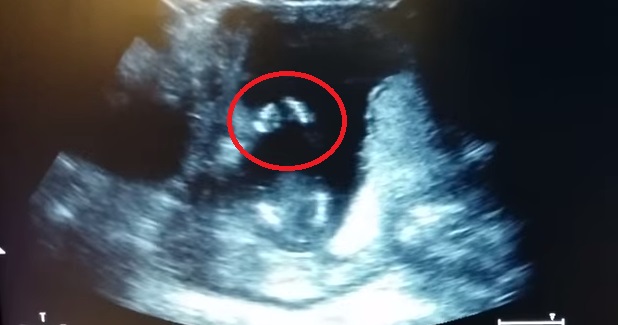

ROMA – Una donna incinta e suo marito vanno dal medico per effettuare un’ecografia alla 14esima settimana di gravidanza. Durante l’esame accade qualcosa di straordinario: il piccolo feto sembra battere le mani quando i genitori iniziano a cantare “Se sei felice e tu lo sai”.

Il video postato su YouTube dall’utente Jen Cardinal è stato probabilmente ritoccato, ma la reazione del bimbo è comunque adorabile. Secondo quanto spiegano i medici, alla 14esima settimana di gravidanza un bimbo riesce a muovere le labbra, inghiottire la saliva. Anche gli organi interni sono formati: diverse le opinioni dei medici sul fatto se sia in grado oppure no di reagire agli stimoli esterni. La teoria prevalente è quella che non sia ancora in grado di fare cose del genere, come muovere aqualche parte del corpo a ritmo di musica.